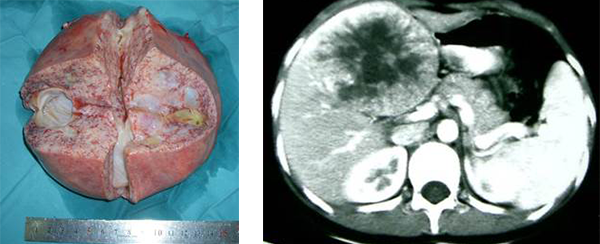

肿瘤肉眼所见为肝内圆形肿块,极少见有蒂与肝脏相连,肿瘤周围有假包膜与正常肝组织分界。多生长较大。剖面肿瘤呈胶冻样,常见出血、坏死和囊肿形成。镜下肿瘤由小细胞构成,有圆形核和不明显的核仁,含少量界限不十分清楚的胞浆。有些则为小梭形细胞和星形细胞,成片或散在于黏液基质内,形成密集区和疏松区交替排列的现象。有时瘤细胞浆呈空泡状,苏丹染色呈阳性反应。电镜下这种细胞很像脂肪母细胞。此外,还可见到成簇或散在的多核巨细胞及间变型大细胞,核形怪异,染色质丰富,染色深,不典型核分裂常见,胞浆丰富粉染,有些胞浆内和间质区可见嗜酸性透明小体,PAS染色阳性。抗淀粉酶消化。这些细胞常见于坏死灶周围,使肿瘤形态很像多形性横纹肌肉瘤,但胞浆内找不到横纹,Myoglobin和Desmin染色呈阴性反应。肿瘤边缘和假包膜内常见腺管结构,腺管上皮常见不典型增生,估计是被肿瘤包围的胆小管。电镜检查:巨细胞内可见有膜包绕的高度嗜锇酸颗粒,肿瘤内还可见到成束紧密交织排列的梭形细胞,很像纤维肉瘤或纤维组织细胞瘤。免疫组化染色:Vimentin和α-1Anti-trypsin呈阳性反应,Cytokeratin,Myoglobin和Desmin呈阴性反应。见图9。

图9:示肝脏肉瘤的手术大体标本所见,男,4岁

图10:示肝中叶肝脏肉瘤CT所见

【临床表现】

为儿童期少见肿瘤,占小儿原发性肝肿瘤的第四位。发病年龄大多6~10岁,亦可见于成人及幼童。临床主要表现为上腹部肿物,伴有发烧、黄疸和体重下降。肿瘤发生于肝内,右叶比左叶多见。该肿瘤生长迅速,恶性度高,晚期转移至肺及骨骼,存活期多为一年左右,预后不良。

实验室检查除个别病例偶见SGOT和碱性磷酸酶异常外,没有其他异常发现,AFP试验多为阴性。血管造影肿瘤常表现血管少,因此有些病例和肝脓肿混淆。超声检查可见囊性和实性病变。

CT提示巨块肿瘤可侵占一或两叶肝。肿瘤呈椭圆形或大分叶状低密度肿块。CT所见取决于大体病理。可为分隔多房的囊性肿物,囊腔大小不一呈水样密度,粗细不匀的分隔为肿瘤的实性部分,密度与肌肉相仿,CT值约35HU。周围有假性包膜。有时肿瘤呈单一大囊腔,内含无定形絮团状阴影,部分呈蜗轮状,内壁见高密度息肉阴影附着示肿瘤内出血。肿瘤亦可以实性为主,内含多数小囊。肿瘤血供多少不定,囊性病变明显的病例,血供一般较少或无血供。增强扫描,实性部分及包膜可有强化,囊性部分增强不明显,CT值在22~28HU,偶见钙化。本病需结合临床、影像学所见与间叶错构瘤鉴别。